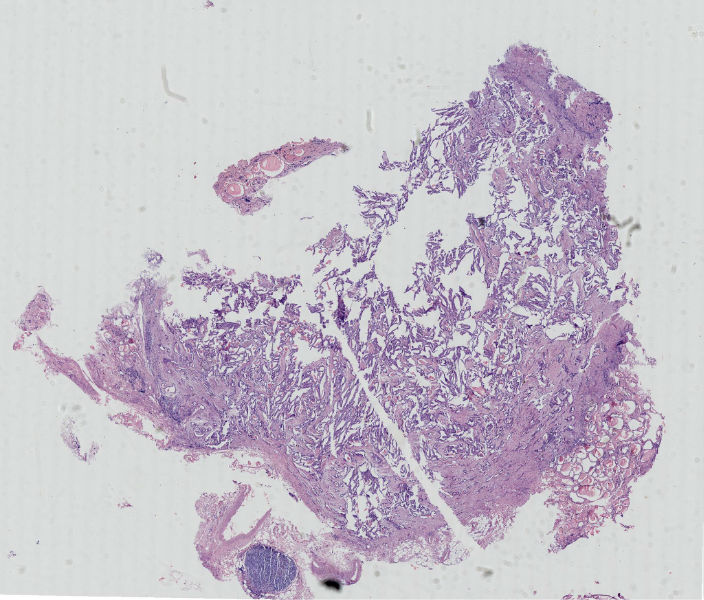

在传一个全景图,

• 图1